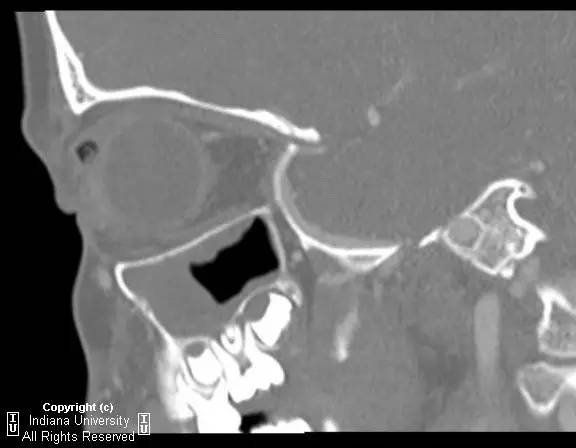

右侧上眼睑软组织肿胀。上眼睑与眼球间可见矩形积气,约1 cmx 0.4 cm x 0.4 cm,并线样影在内穿行。眼球及晶状体正常。眶隔后及眶内软组织无肿胀、血肿或脂肪条纹提示为创伤性。无对比剂外渗。无对急性骨异常。右侧上颌窦粘膜增厚。

【诊断】右上眼睑和眼球间木片存留

There is a piece ofwood between the superior right eyelid and the globe.

CT为评价眼眶创伤的一线方法,可帮助评估眶内异物的存在。木片可能很难与气体及骨折片区分。木片CT的表现取决于其含水量,干松木密度较低,而鲜松木密度高,取决于空气与水的含量。干木因网状基质可以区别于空气。MR对干木的检查可能更敏感,在T1加权图像相对脂肪呈低信号。